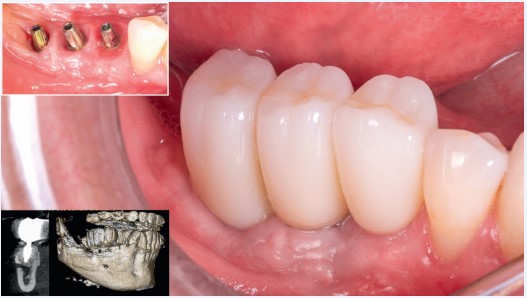

Etapa 3 – Instalação de implantes dentários

Após três meses, constatou-se a neoformação óssea adequada. Assim, foram instalados três implantes cone-morse Maestro (Implacil Osstem) com estabilidade primária satisfatória e aproximadamente 20 N·cm de torque de inserção (Fig. 8); após a instalação dos implantes, para ganho de volume tecidual e diminuição da remodelação do tecido ósseo, foi realizada a colocação de enxerto ósseo xenógeno com colágeno (Extragraft, Implacil Osstem) (Fig. 9). Três meses após a osseointegração, os implantes foram reabertos para instalação dos pilares protéticos (Ideale, Implacil Osstem) e confecção das coroas provisórias, seguidas da finalização com as cerâmicas definitivas unitárias em zircônia monolítica após mais três

meses de terapia (Figs. 9 e 10).

Figura 8: Reabertura após o período de 3 meses para a instalação de 3 implantes Maestro (Implacil Osstem) de 3,5 × 10 mm

Figura 9: Cobertura da área enxertada com substituto ósseo xenógeno (Extragraft, Implacil Osstem)

Figura 10: Instalação de Pilares Ideale (Implacil Osstem) e provisorização após 3 meses da instalação dos implantes e finalização das cerâmicas após 6 meses. Controle de 2 anos em TCFC.